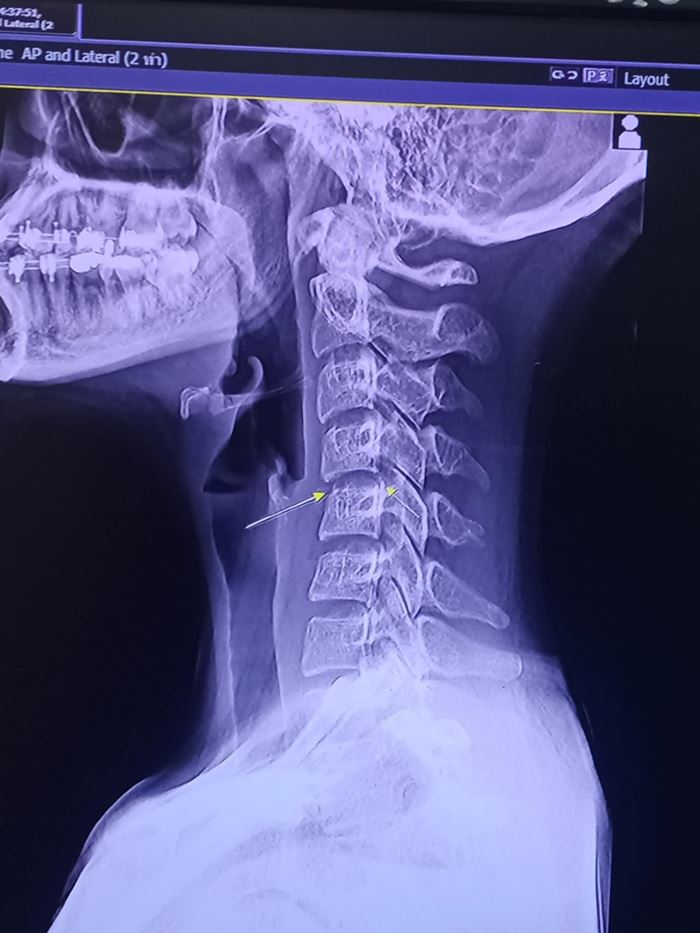

โดยจากโพสต์ของ ผิง ชญาดา เมื่อวันที่ 5 พฤศจิกายน มีการเปิดภาพเอกซเรย์กระดูกบริเวณคอ พร้อมระบุว่า

"หนูไม่รู้จะเริ่มยังไงดี คนทักถามเยอะมากว่าเป็นอะไร คืองี้หนูไปนวดที่ที่หนึ่งมาค่ะ ในอุดรฯ อาการตอนก่อนไปนวดคือหนูปวดแค่ไหล่เฉย ๆ ค่ะ หนูไปนวดครั้งแรกอาการตอนนวดเสร็จปกติค่ะ ผ่านมา 2 วันหนูเริ่มปวดท้ายทอย หนูนึกว่าเป็นอาการปวดของการนวดปกติ (มีบิดคอนะคะ)